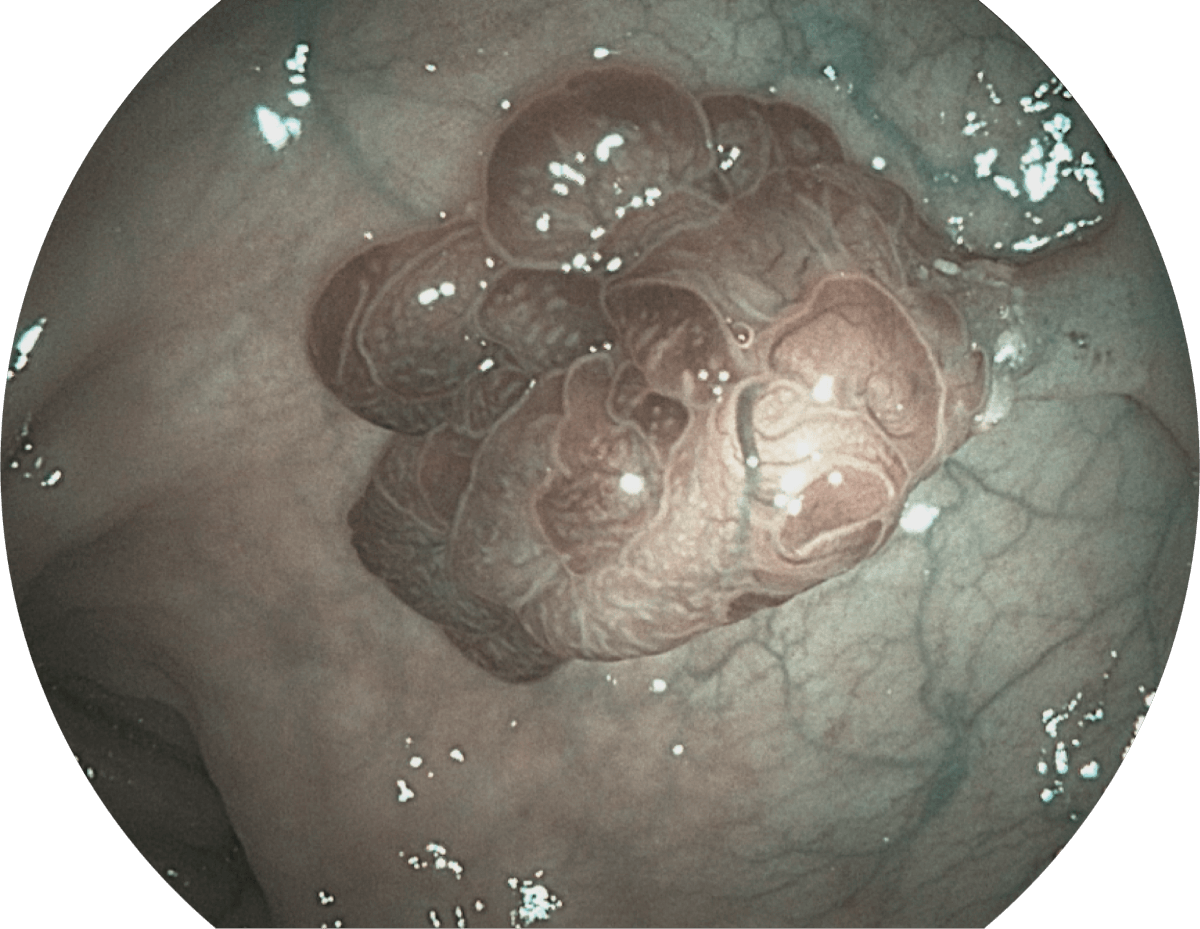

具有聚谱成像技术(SFI)及光电复合染色成像技术(VIST),可完美呈现粘膜细节及病变特征。

( Versatile Intelligent Staining Technology, VIST )

SFI

VIST